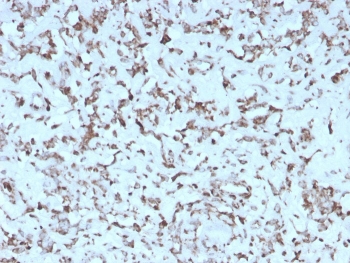

IHC staining of FFPE human liver with recombinant Cytochrome C antibody (clone rCYCS/1010). HIER: boil tissue sections in pH 9 10mM Tris with 1mM EDTA for 20 min and allow to cool before testing.